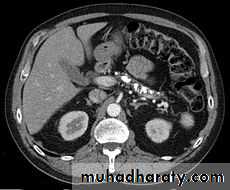

Chronic pancreatitis

Pancreatic carcinoma

Irresectable